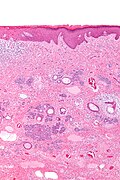

| LM | typically well-circumscribed cell nest in the superficial dermis, surrounding by a fibrous stroma, basaloid cells - usu. with peripheral palisading +/-surround keratin-filled cysts, fibroblasts-like cell aggregate, similar to a follicular papillae (papillary-mesenchymal body) |

Features:[3]

- Well-circumscribed cell nest in the superficial dermis.

- Surrounding by a fibrous stroma.

- Basaloid cells with peripheral palisading.

- +/-Surround keratin-filled cysts.

- Fibroblasts-like cell aggregate, similar to a follicular papillae (papillary-mesenchymal body).

Trichoepithelioma - low mag. (WC/Nephron)

- Trichoepithelioma - intermed mag.jpg

Trichoepithelioma - intermed. mag. (WC/Nephron)